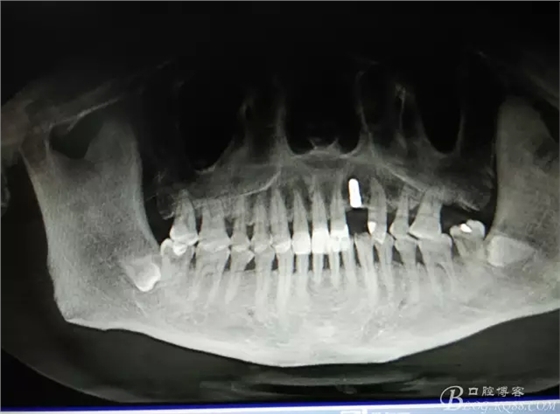

圖1.術(shù)前的CBCT檢查:22缺失。